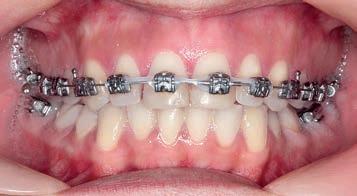

Figs. 9a–c: Situation after 1 month of correction with Sagittal First approach. – Figs. 10a–c: Situation after 2 months of correction. – Figs. 11a–c: Situation after 3 months of correction: Class I achieved. – Figs. 12a–c: Situation after 4 months of treatment (3 months of Motion sagittal treatment and 1 month in fixed appliances). .014 x .025 wire with power chain to close the spaces between the incisors. – Figs 13a–c: Situation after 7 months of treatment (3 months of Motion sagittal treatment and 4 month in fixed appliances). .019 x .025 archwire was engaged with power chain to retract the anterior segment and bring it into the final desired position. – Figs 14a–c: Final situation achieved after 11 months of treatment (3 months of Motion sagittal treatment and 8 months of Carriere SLX fixed appliance therapy).